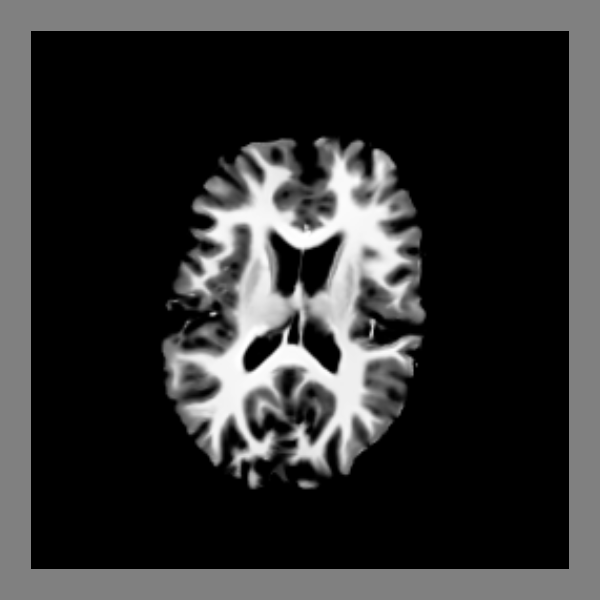

Render slices from T1 with a specific value range#

The T1 has usually a higher range of values than what can be visualized in an image. We can set the range that we would like to see.

The slice function will read data and resample the data using an affine

transformation matrix. The default behavior of this function is to show the

middle slice of the last dimension of the resampled data.

slice_actor = actor.slicer(data, affine=affine, value_range=value_range)

The slice_actor contains an axial slice.

window.record(scene=scene, out_path="slices.png", size=(600, 600), reset_camera=False)

Simple slice viewer.